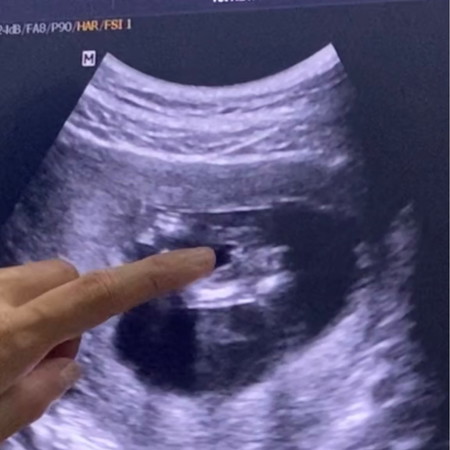

ท้องแรกค่ะ ดูไม่เป็นเลย น้อง12w5 d

ช่วยดูหน่อยค่ะแม่ๆ ว่าน้องเป็น ผช หรือ หญิง จ้า

หมอว่ายังไงคะแม่ เรามองจากรูปเห็นเหมือนมีอะไรโผล่ น่าจะผู้ชาย😆